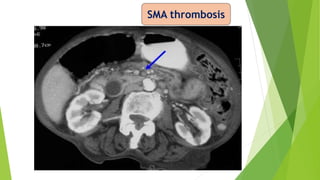

SMA occlusion

SMA thrombosis

Gas in Mesenteric Vein Gasin Bowel wall (Pneumatosis intestinalis) CECT abdomen

CECT showing in ExtensivePortal Venous Gas